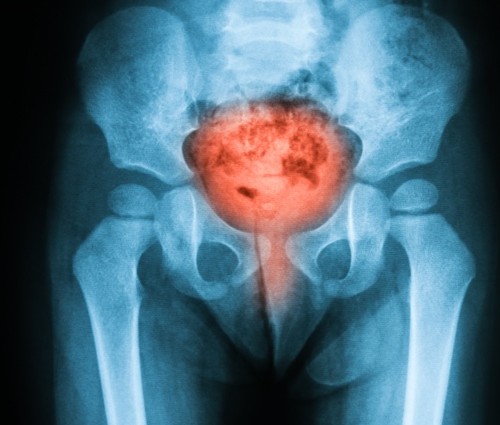

Nýrnasteinar eru smáar harðar útfellingar kalsíumkristalla sem safnast fyrir í nýrnaskjóðu. Nýrnaskjóða rennur saman við þvagleiðara sem nær niður í þvagblöðru. Steinarnir verða til ef styrkur kalsíumkristallanna í... Lesa meira